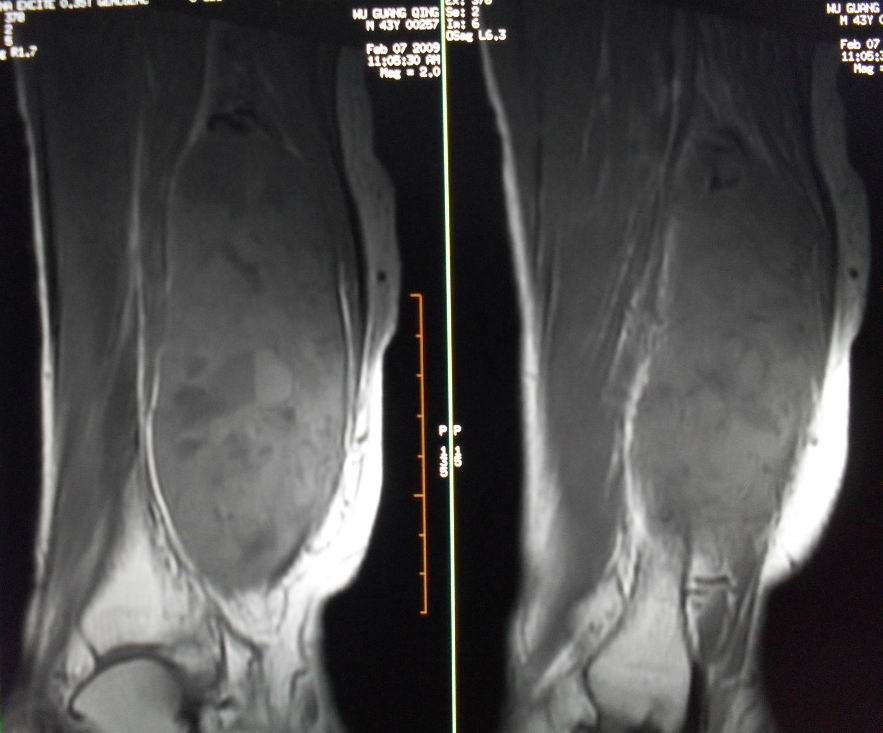

患者男43,右小腿后部软组织肿块2~3年,近期增大明显。平扫加强化。已手术。

1)呈等长t1混杂t2信号,其内见多发类圆形长t1长t2异常信号,病灶主要沿肌间隙生长,但有完整的包膜.gd_dtpa显示:病灶呈明显不均匀的强化,但未见迂曲的强化血管影.

考虑神经鞘瘤可能性大

本病例软组织肿块大,内信号不均匀,有多个囊变区,包膜完整,本片经山东省医学影像研究所mri室王主任会诊术前考虑良性肿瘤,不排除恶变,在北京某医院手术,穿刺及术后病理均为良性,未发现恶变。

本病例软组织肿块大,内信号不均匀,有多个囊变区,包膜完整,本片经山东省医学影像研究所mri室王主任会诊术前考虑良性肿瘤,不排除恶变,在北京某医院手术,穿刺及术后病理均为良性神经鞘瘤,未发现恶变。[face=宋体][/face]